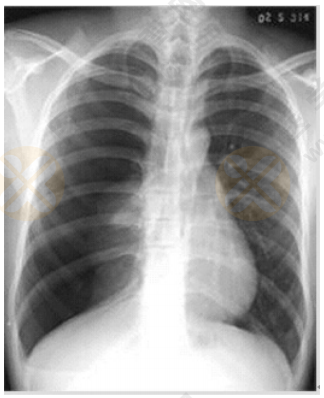

根據(jù)下圖所給X線片分析臨床意義。(5分)